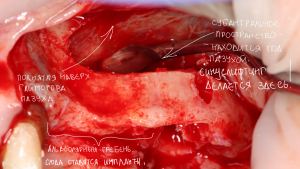

Распространено ошибочное мнение, что синуслифтинг – это операция в гайморовой пазухе. На деле, она проводится не «в», а «под» ней, что также следует из названия (рис. 1,2).

Рисунок 1, 2. Синуслифтинг – операция не «в-», а «под» гайморовой пазухой.